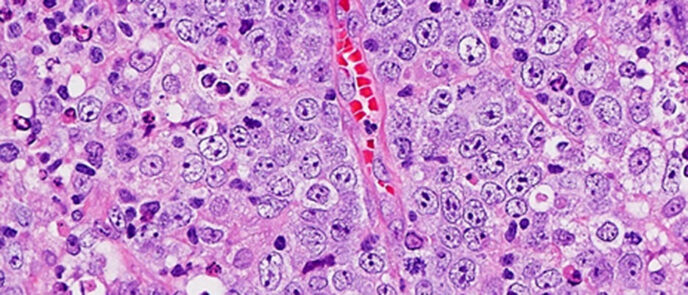

Mehr erfahren zu: "Neoadjuvante Chemo-Immuntherapie bei Lungenkrebs: DGP macht auf Veränderungen der Pathologie aufmerksam" Neoadjuvante Chemo-Immuntherapie bei Lungenkrebs: DGP macht auf Veränderungen der Pathologie aufmerksam Anlässlich des Deutschen Lungentags am 28. September 2024 berichtet die Deutsche Gesellschaft für Pathologie (DGP), wie die neoadjuvante Chemo-Immuntherapie bei Lungenkrebs die Arbeit der Pathologen verändert.